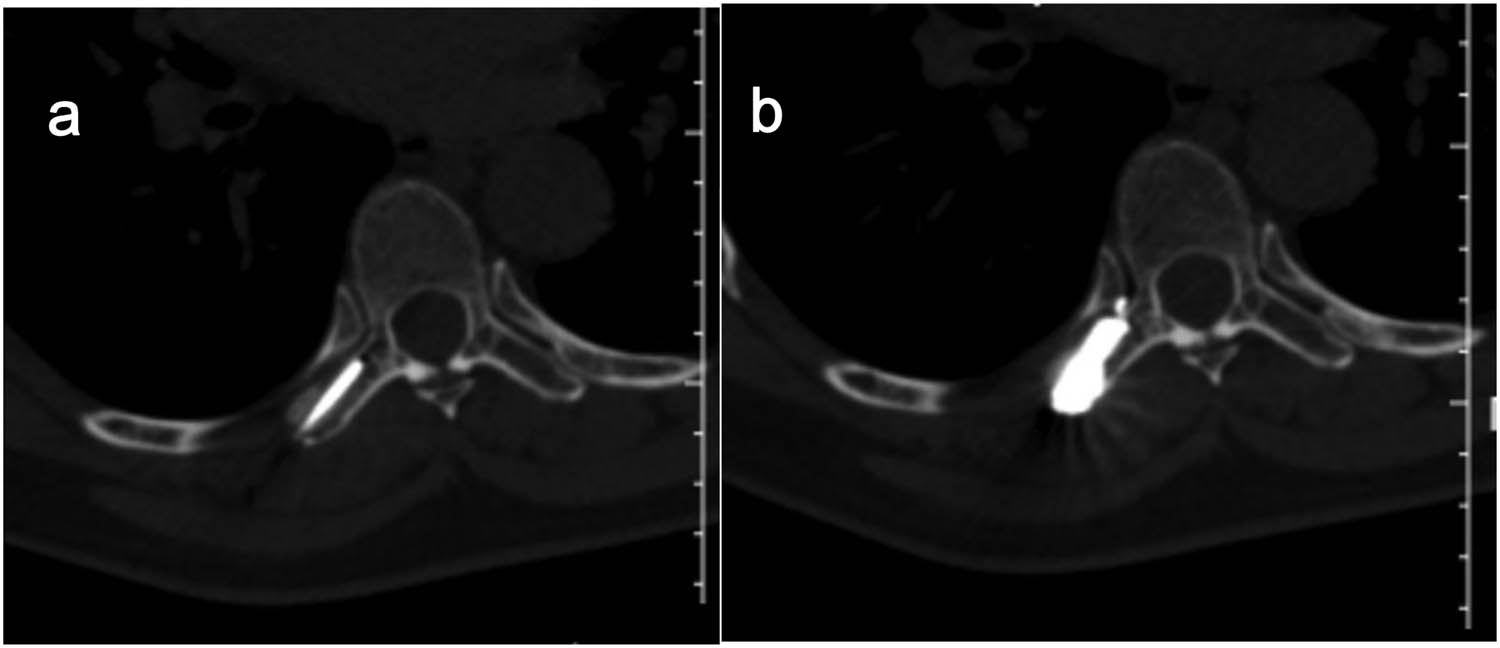

All procedures were performed using a Siemens Sensation 64 CT-scan (Siemens Healthcare, Erlangen, Germany) in the prone or supine position depending on the position of the lesion. The target lesion and needle path were located by non-enhanced helical CT acquisitions. Preoperative invasion range and destruction degree of adnexal tumor were determined and the injection route was planned according to X-ray, CT-scan, and MR (including enhanced) image data. After accurate marking of the skin and in strictly aseptic conditions, local subcutaneous injection of lidocaine 1% was performed at the defined skin entry point and an 11-gauge 15 cm co-axial needle (Dragon Crown Medical Co., LTD, China) was introduced step by step under CT-fluoroscopy (Figure 3a and b). After the needle was punctured into the right transverse process of T7 (adjusted during CT guidance), a 16G-gauge 20 cm MWA probe (ECO-100AL6, Nanjing Yigao Medical Technology Co., LTD, China) was advanced into the osseous lesions of T7’s right transverse process. Then connect the ablation needle to the ablation instrument (ECO-100A1, Nanjing Yigao Medical Technology Co., LTD, China), adjust the power to 70 W, and ablate twice for 2 min each time (Figure 4a). During the ablation process, the patient’s vital signs and the movement of the lower limbs were observed. After the ablation needle was withdrawn, the polymethylmethacrylate bone cement (PMMA, Heraeus Medical Ltd, German) was prepared in the appropriate ratio (powder (g)/liquid (mL) = 2:1) and was pushed with a cement-filled cannula (Dragon Crown Medical Co., LTD, China). The distribution of the bone cement is observed until it has diffused to the edge of the lesion (Figure 4b). After the bone cement has been filled, the cannulas were removed and the patient is returned to the ward for recovery.

Localization is performed on the body surface by X-ray (a) and puncture is performed under CT guidance (b).